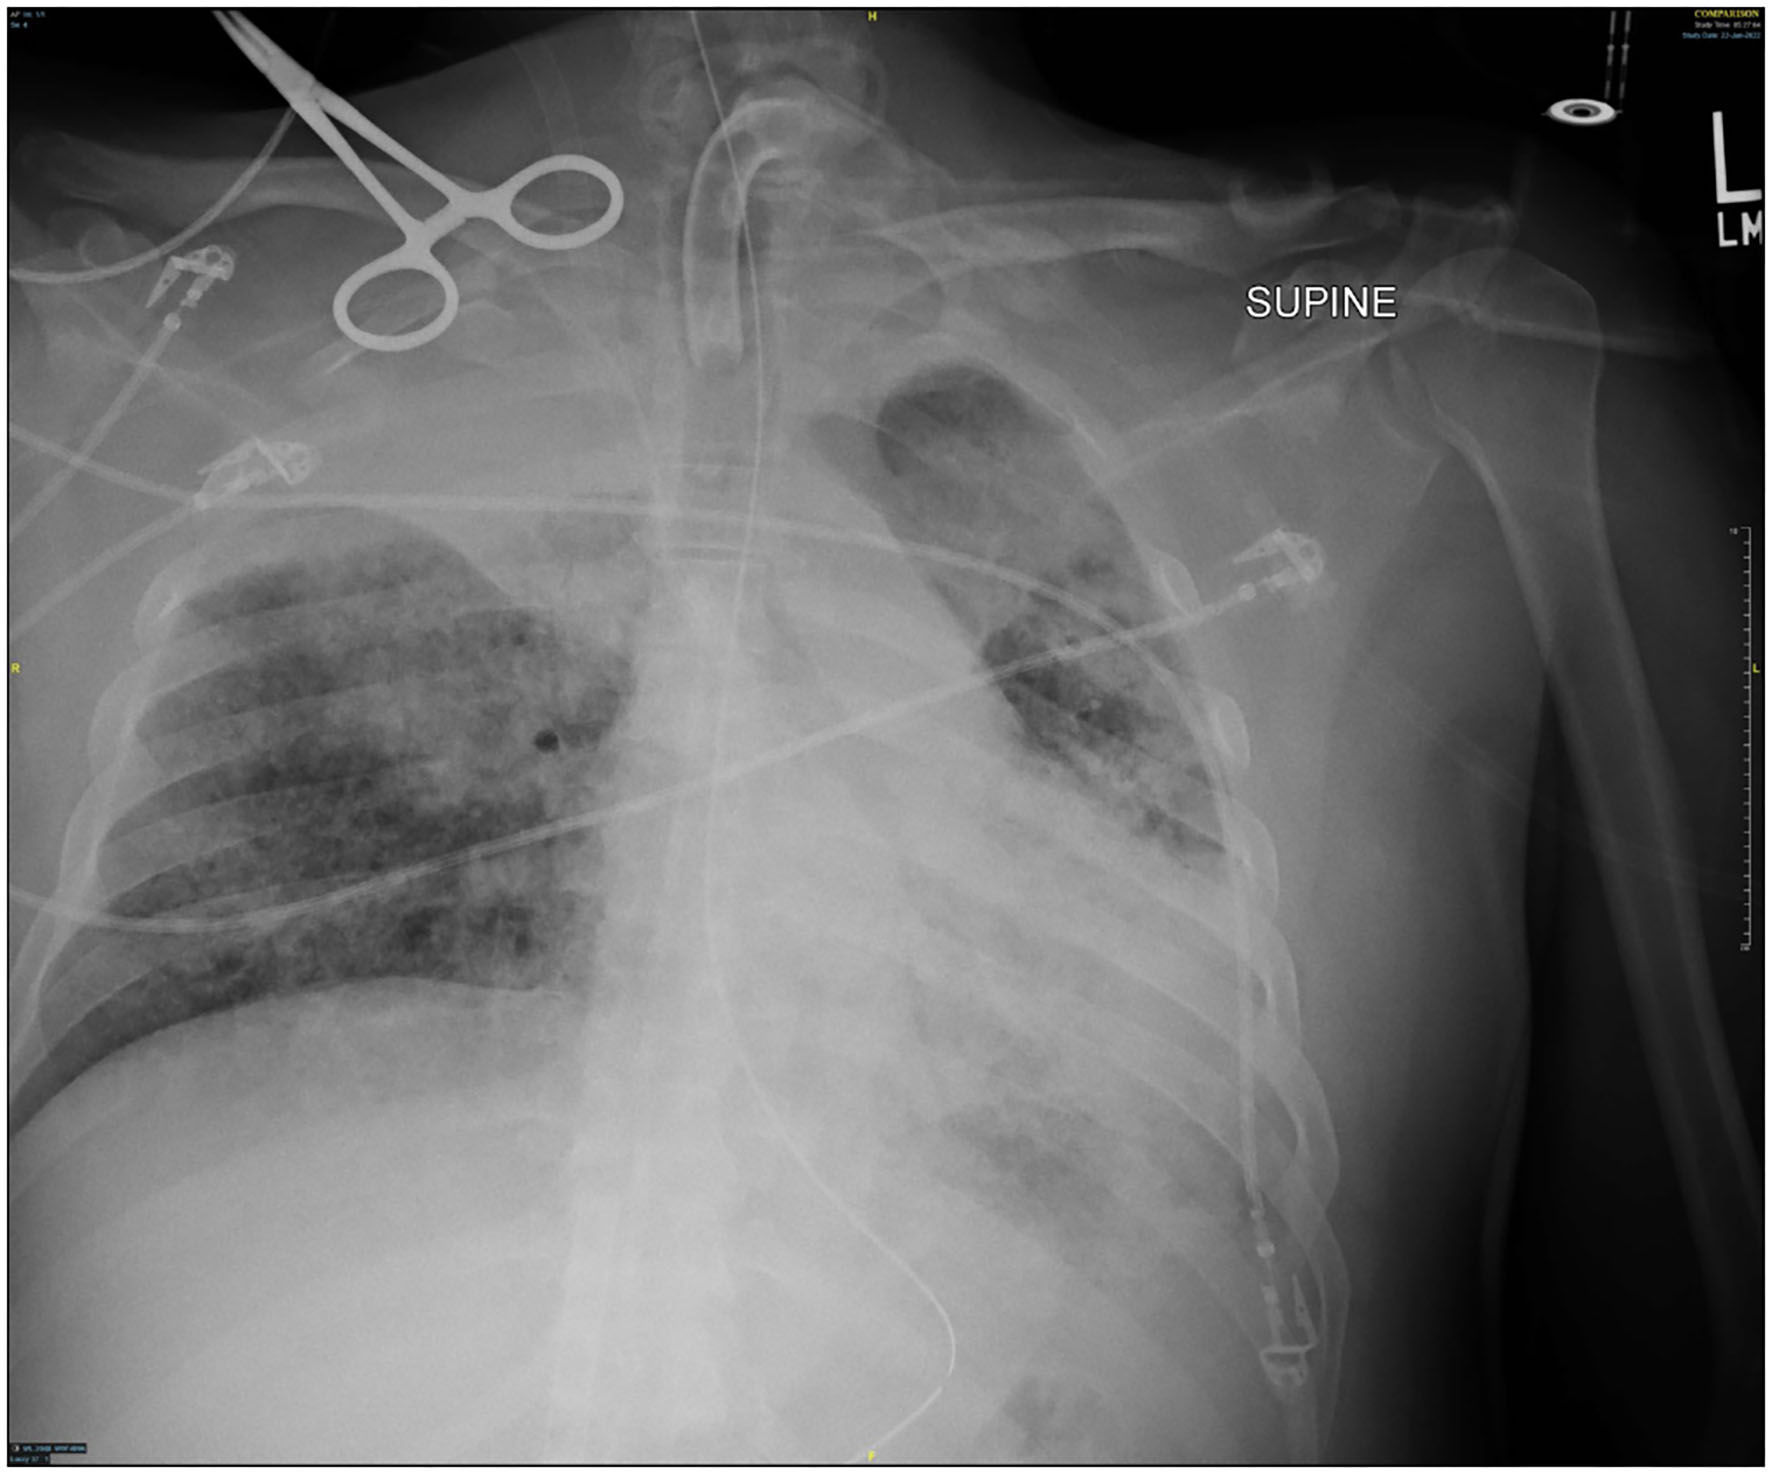

Figure 5

Chest x-ray 2 days after resuming ventilator.

Though active hemorrhage had ceased during this time of mechanical ventilation, the patient's chest x-ray continued to exhibit bilateral opacification (Figure 4). On hospital day #20 (VV ECMO day #13), a repeat bronchoscopy was performed to remove clot which had formed from the bilateral bronchi with some radiographic progress. Due to improvement in active hemoptysis, the ventilator was restarted with a minimum TV of 250 cc (IBW x 4 cc) after 48 hours of complete discontinuation of ventilator. Serial declotting bronchoscopies were then performed utilizing various bronchoscopic instruments including a basket, biopsy clamp, and brush to facilitate clot retrieval. This process was continued daily until all visible clot was removed and chest x-ray demonstrated decreased opacification (Figure 5). Bronchoscopy was performed a total of 14 times. Antiplatelet therapy was then resumed, and there was no recurrence of bronchial hemorrhage, although systemic heparin and anti-platelet agents were held.